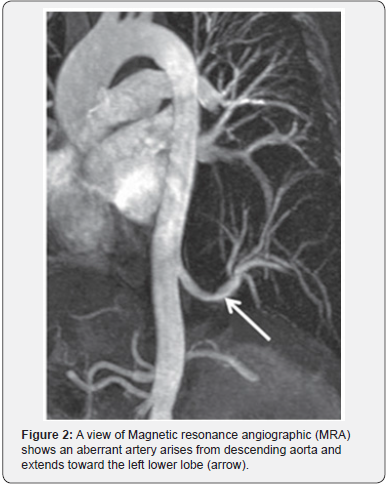

On imaging studies for PS, there may be no specific findings on chest X-ray examination, however, there may be a pulmonary abnormality which is usually solid opacity and occasionally it may be air filled with or without air fluid level due to fistula formation to adjacent bronchi or air drift through the channels of Lambert [13,14]. Nowadays, the useful diagnostic methods of PS are CT angiography (CTA), magnetic resonance angiography (MRA), and digital subtraction angiography (DSA) which allow identification of the aberrant arterial supply (Figures 1 & 2) [8].

The standard computed tomography (CT) scan may show indirect signs of abnormal arteries in cases with PS, which may indicate further use of contrast-enhanced CT scan or enhanced MRI if the affected pulmonary area and thoracic aorta are connected by rat-tailed tissue. The use of CTA has the advantage of an optimal detection of the parenchymal abnormality as well as the arterial and venous anatomy with shorter scan times than those of MRI decreasing the need for prolonged sedation in children; however, MRI has an advantage of the absence of radiation risks [15].